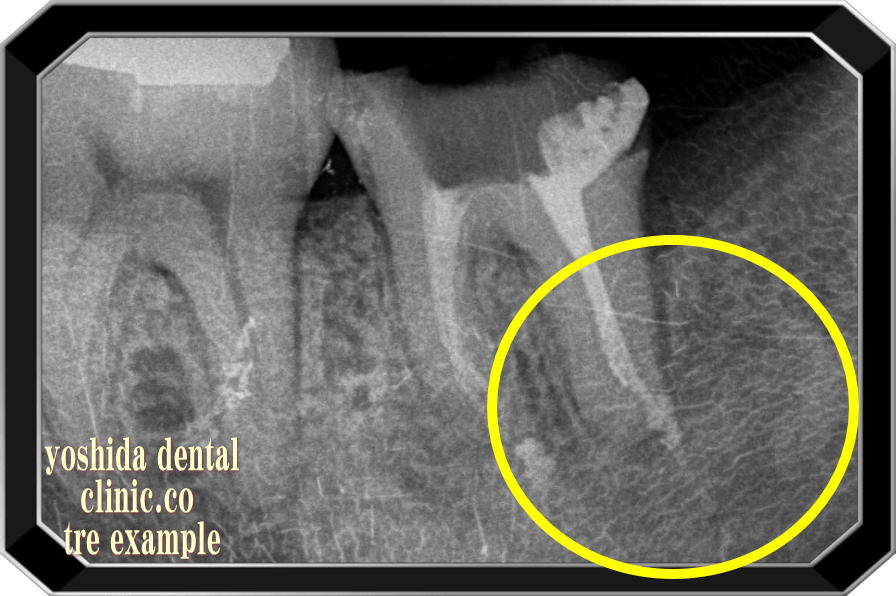

NI-TIファイルを用いた保険による根管治療前・後

根尖病変 R→ 根尖病変改善

根管治療前 根管治療後の骨再生

根の先の炎症で骨が溶けています(黒くなっている部分)。あなたならどうしますか?

抜歯されますか?根の治療を保険治療で行い保存されますか?

当院での保険治療後右の写真では骨が治癒し白さ(骨)を取り戻しています。

~全症例マイクロスコープは使用していません~

~保険にて根管の治療を行って治癒しています~